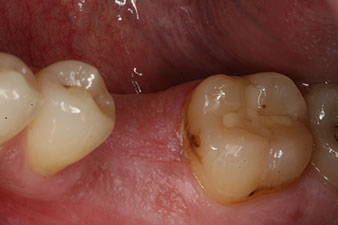

Fig. 6 : Dix semaines plus tard, on a retiré le façonneur de gencive qui avait été inséré après la pose de l’implant. Dans la direction linguo-buccale, la valeur ISQ est restée pratiquement inchangée, à 63 (sonde de mesure à proximité, à une distance de 2-3 mm).

L’implant a été mis à nu deux mois plus tard et un façonneur gingival a été introduit par vissage (pas de photo).

Après cicatrisation des tissus mous, la stabilité de l’implant a été mesurée une nouvelle fois avant la pose de la restauration prothétique.

Les deux valeurs étaient pratiquement inchangées, situées entre la plage moyenne et la plage haute - la valeur la plus basse étant toujours utilisée comme valeur de référence qui détermine le traitement.

Par conséquent, il a été possible d’enregistrer une ostéo-intégration réussie et une stabilité biologique correcte, permettant également de prendre une empreinte durant la même séance.